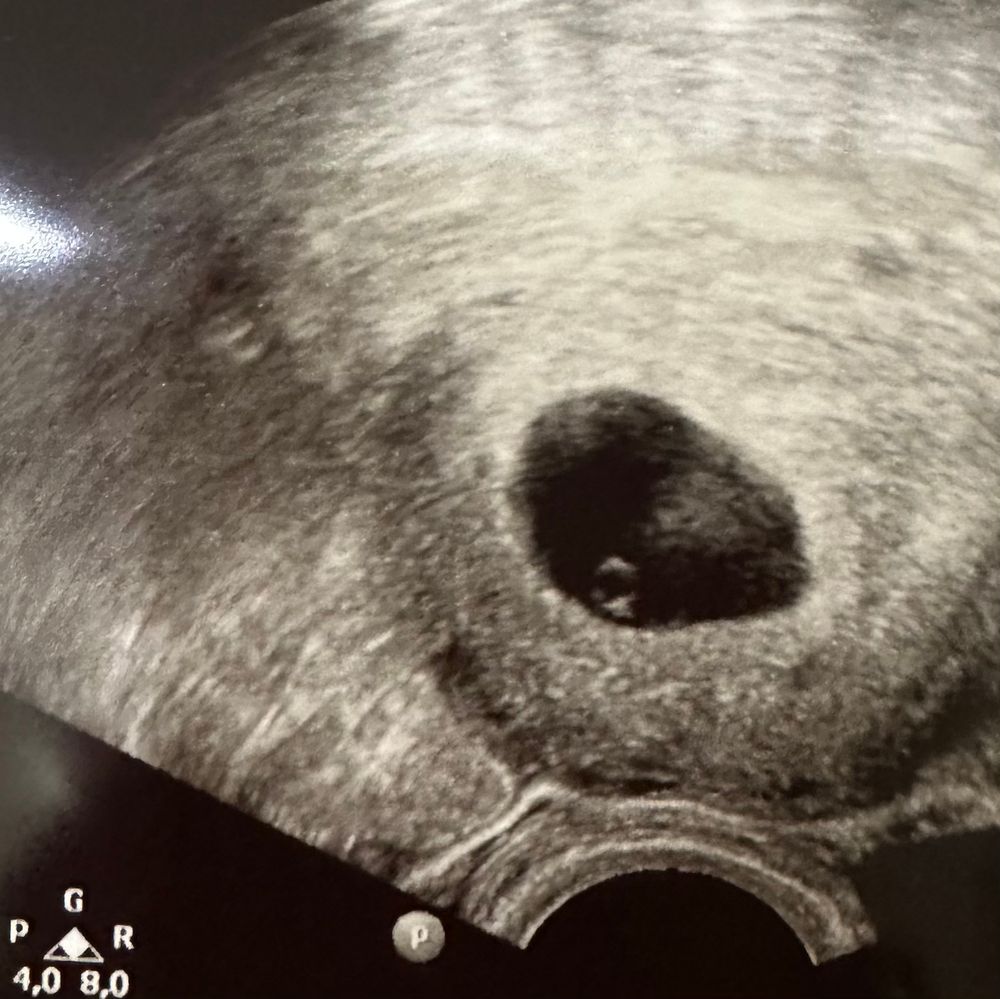

Изображение Ирина, я сходила, всё ок, всё есть, даже колечко бриллиантовое, только сб отложили на неделю, так сказала ре) ладно подождем 🙏🏻

Женечка , отлично! Рада за вас! Легкой вам беременности! Красивая фотка!👍